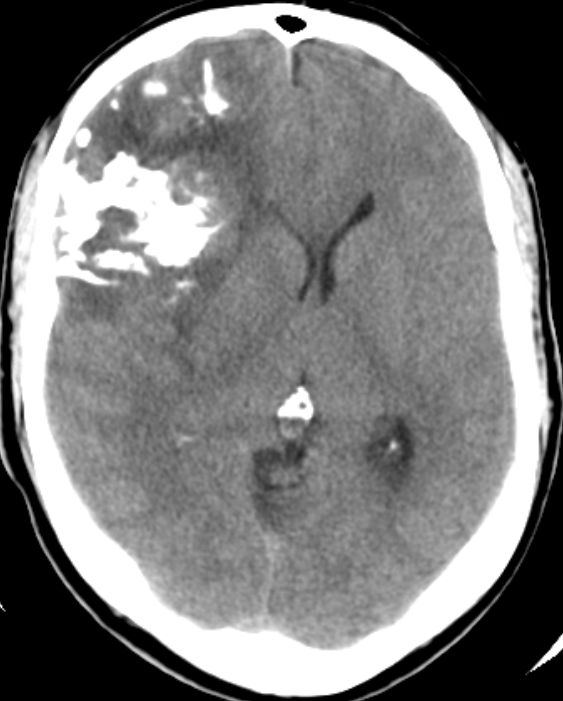

CT

46-jähriger Mann mit anaplastischem Oligodendrogliom WHO-Grad III rechts fronto- parieto-temporal, keine 1p19q-Deletion, IDH-1-Mutation, Ki67 12%.

Der Patient erlitt beim Autofahren einen epileptischen Anfall mit Myoklonien des gesamten Körper und Bewusstlosigkeit.